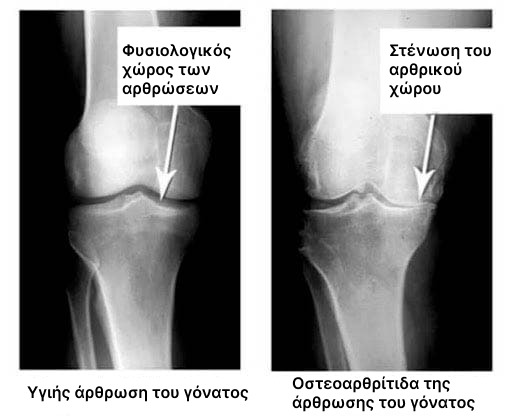

Η καθιστική ζωή, το άγχος, η υπερβολική κατανάλωση αλατιού και ζάχαρης στη διατροφή - όλα αυτά μαλακώνουν τον ιστό των χόνδρων, τον φθείρουν και τον κάνουν πιο λεπτό. Με κάθε νέα κίνηση, ο χόνδρος φθείρεται και παραμορφώνεται, τα οστά αρχίζουν να τρίβονται το ένα πάνω στο άλλο, προκαλώντας αφόρητο πόνο.

Η ρευματοειδής αρθρίτιδα και η οστεοαρθρίτιδα μπορούν να οδηγήσουν σε αναπηρία μέσα σε 3 έως 5 χρόνια από την έναρξη της νόσου και να μειώσουν το προσδόκιμο ζωής των ασθενών κατά 15 έως 20 χρόνια!